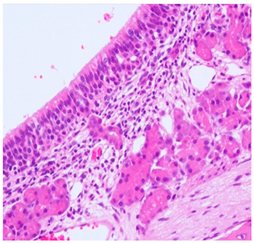

![]() | Grade 1: Mild lymphoplasmacytic infiltration in the lamina propria. |

![]() | Grade 2: Moderate lymphoplasmacytic infiltration in the lamina propria with the lymphocytic infiltration of the epithelium lining, resulting in some disorganization and disruption of the epithelium and loss of cilia. |